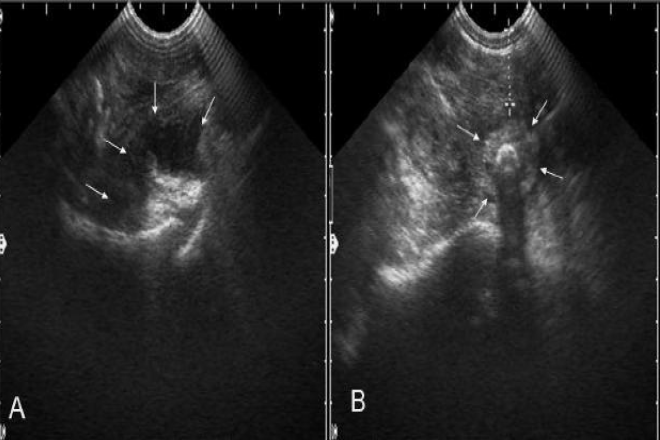

Carcinoma ductal infiltrante de mama en el hombre

El cáncer mamario en hombres es una enfermedad rara e infrecuente de investigación limitada. El primer caso documentado fue descrito en Inglaterra. Esta condición causa 1 % de todos los carcinomas de mama y menos de 1 % de las neoplasias malignas en hombres. Su